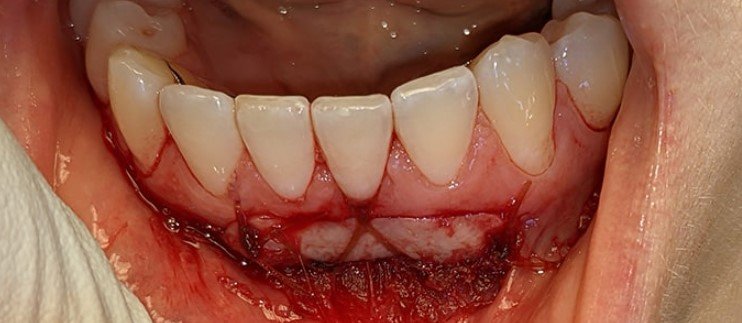

Signs of Gum Graft Failure

There are 6 clear signs of gum graft failure:

- Persistent white tissue sloughing

- Severe pain beyond 7 days

- Pus or infection at the surgical site

- Graft detachment or movement

- Increasing recession after surgery

- Prolonged redness and swelling

Immediate periodontal evaluation is required.

What does a failed gum graft look like?

A failed gum graft often appears as a large, non-pink patch of white or gray tissue that may eventually detach from the tooth.